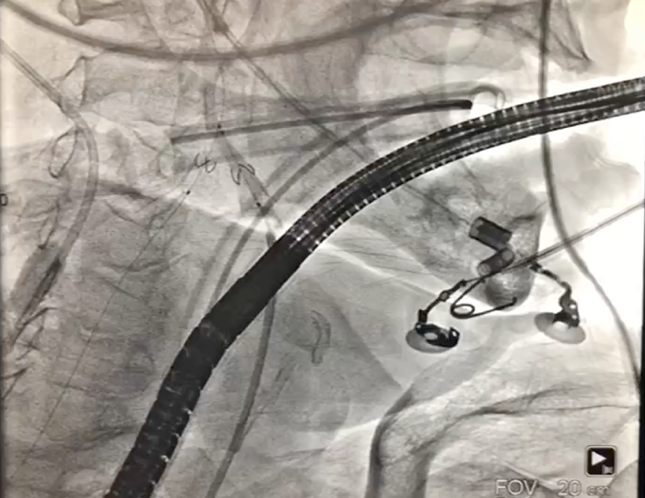

1、经右股动脉将Emboshield Nav6放栓塞装置输送至左、右颈内动脉。

3、按照既定策略,选择24 mm VitaFlow微创瓣膜,于180 bpm快速起搏下,快速一次性释放。

主动脉根部造影示瓣膜位置合适(深度2 mm),轻度瓣周漏。遂释放瓣膜,撤回脑?;ぷ爸?,手术圆满成功。